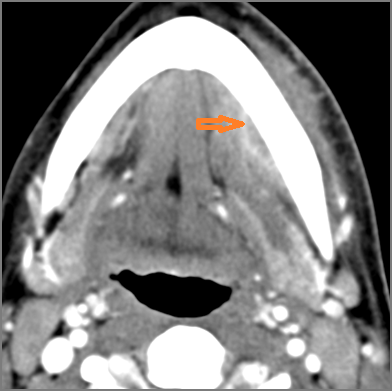

30-year old male with left facial swelling and tenderness mainly in the submandibular space. Primary clinical suspicion was an odontogenic infection.Exam

CT: Contrast- enhanced CT of the maxillofacial region and neck and related anatomy with images obtained in the balanced or venous vascular phase to ensure optimal visualization of both arterial and venous structures as well as possible reactive changes around infected collections. 0.5-3.0 mm thick sections were obtained in the axial plane and reformatted 3D and/or in the coronal and sagittal planes and viewed inter actively in 3 dimensions at the computer work station.